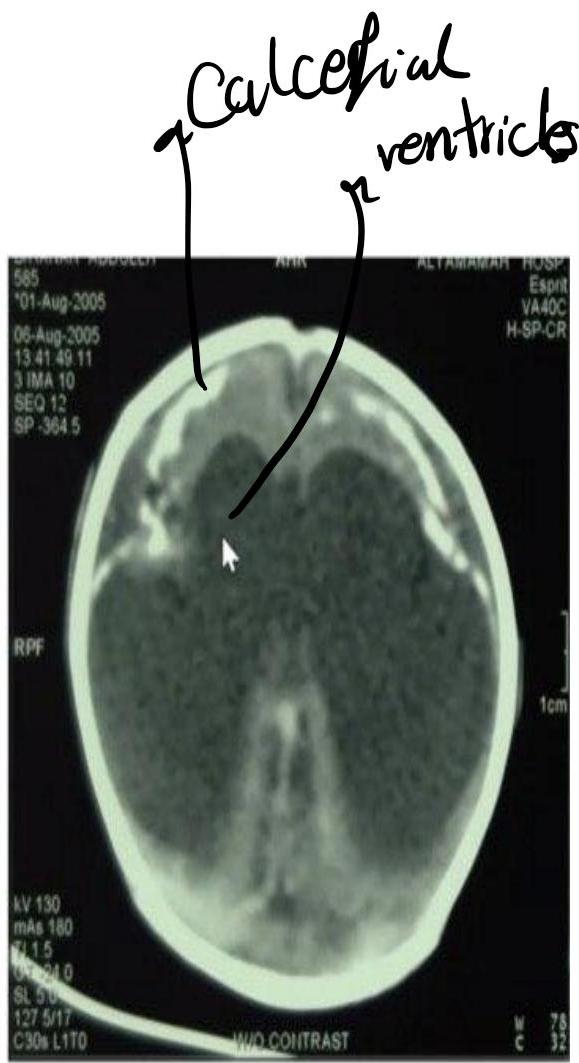

CMV Infection

Diagnosis? CMV.

CT finding? Periventricular calcification (vs Toxo which is scattered).

Findings:

- Hepatosplenomegaly

- Microcephaly

- Jaundice

- Hearing loss

- Non-blanching rash

- Small for gestational age

- Calcification around the ventricles (C-shape)

- History: Mother with mild febrile illness in 1st trimester

Memory aid:

- C-shape calcification = CMV